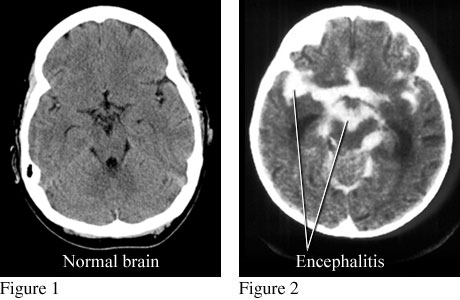

CT scans of normal brain and brain with encephalitis

Figure 1 is a computed tomography (CT) scan of a normal brain. Figure 2 is a CT scan that shows an accumulation of contrast material in infected areas and around the brain from encephalitis.